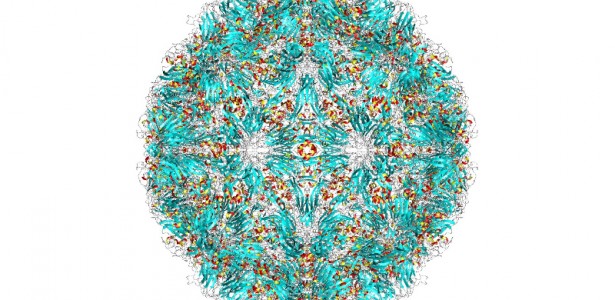

Um estudo da Universidade de São Paulo (USP) revela que tecidos como amígdala e adenoide podem atuar como "esconderijos" para o rinovírus, principal causador de resfriados e responsável por uma grande parte das infecções respiratórias globalmente.

O aspecto inovador do estudo é que, além de infectar o epitélio superficial, o rinovírus também alcança camadas mais profundas das amígdalas e adenoides, afetando linfócitos B (produtores de anticorpos) e T CD4 (reguladores da resposta imunológica). Esses linfócitos têm uma vida útil longa e desempenham um papel fundamental na memória imunológica. Surpreendentemente, o rinovírus persiste nessas células, semelhante ao que ocorre com os vírus herpes e HPV.

Este estudo sobre o rinovírus e sua persistência nos tecidos linfoides oferece novas perspectivas no entendimento das infecções respiratórias em crianças. O artigo completo, intitulado "Rhinovirus infects B and CD4 T lymphocytes in hypertrophic tonsils in children," pode ser acessado aqui.